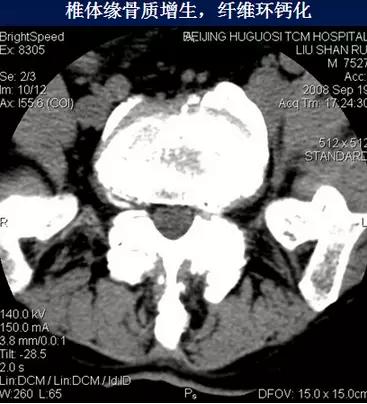

4、纤维环钙化